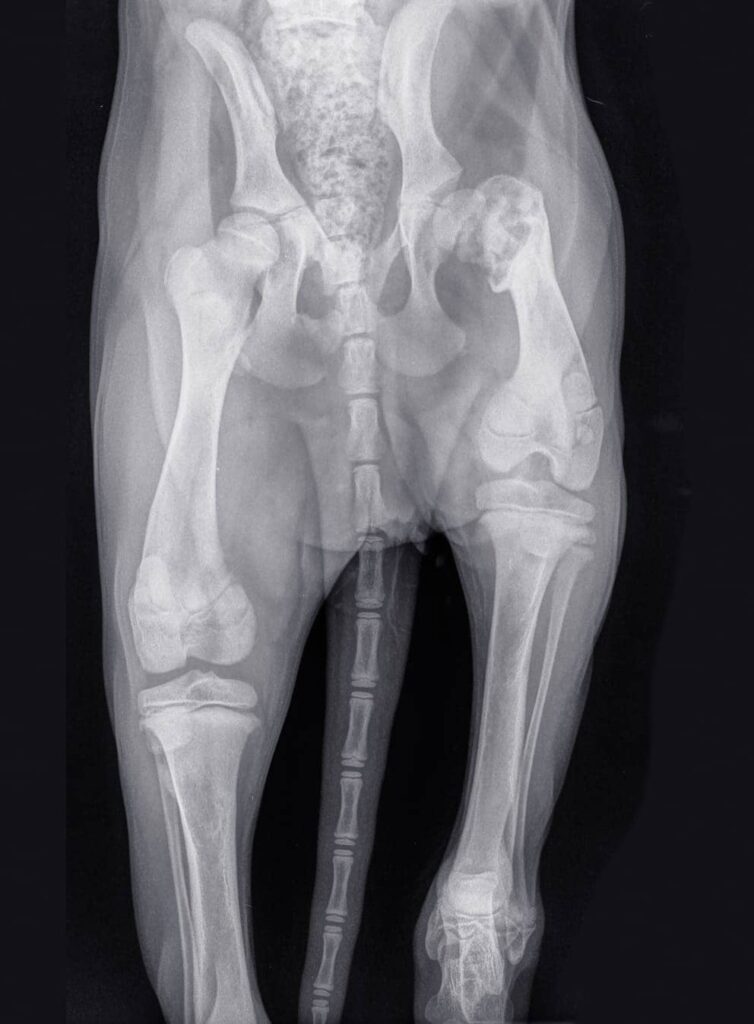

Radiographie

C’est l’étape clé pour confirmer la dysplasie et évaluer son degré. La radiographie permettra de voir exactement ce qui se passe au niveau des hanches du chien, et aidera à déterminer le meilleur traitement à suivre.